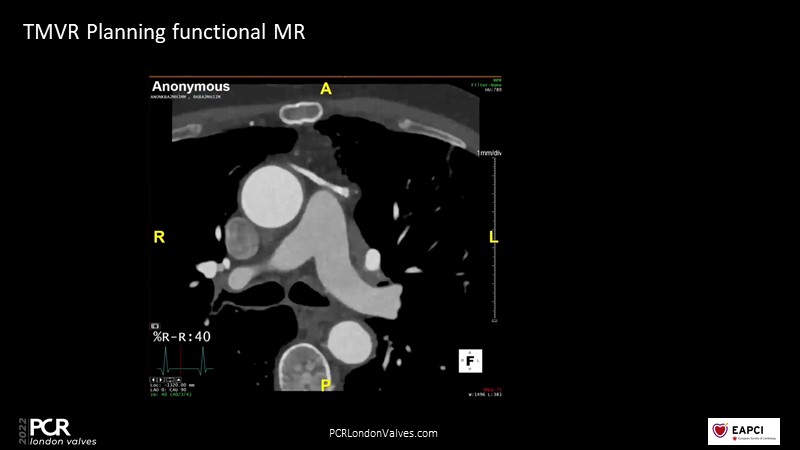

Transcatheter mitral valve replacement - From planning to final assessment

In this session, a panel of experts share their experience with transcatheter mitral valve replacement and more specifically new planning and guidance tools using multiple imaging modalities.

- To leverage CT planning for a better prediction of outcomes in transcatheter mitral valve procedures

- To understand and discover the use of new planning and guidance tools using multiple imaging modalities